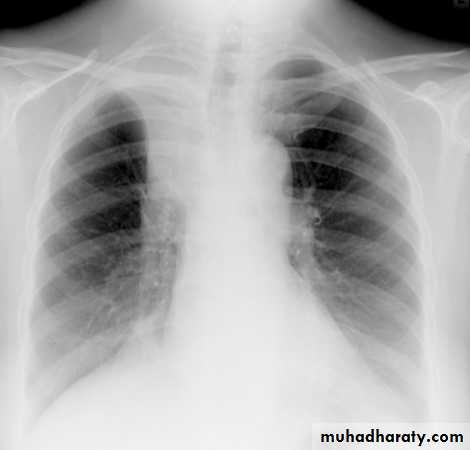

Lung abscess is a circumscribed collection of pus within the lung, is are potentially life threatening. They are often complicated to manage and difficult to treat

Lung abscesses are divided according to their duration into acute (< 6 weeks) and chronic (> 6 weeks) .

A primary abscess is one which develops as a result of primary infection of the lung. They most commonly arise from aspiration, necrotising pneumonia or chronic pneumonia, e.g. pulmonary tuberculosis

Some organisms are particularly prone to causes significant necrotising pneumonia resulting in cavitation and abscess formation. These include :

Staphylococcus aureus

Klebsiella sp: Klebsiella pneumonia

Pseudomonas sp

Plain film

The classical appearance of a pulmonary abscess is a cavity containing an air-fluid level. In general abscesses are round in shape, and appear similar in both frontal and lateral projections.